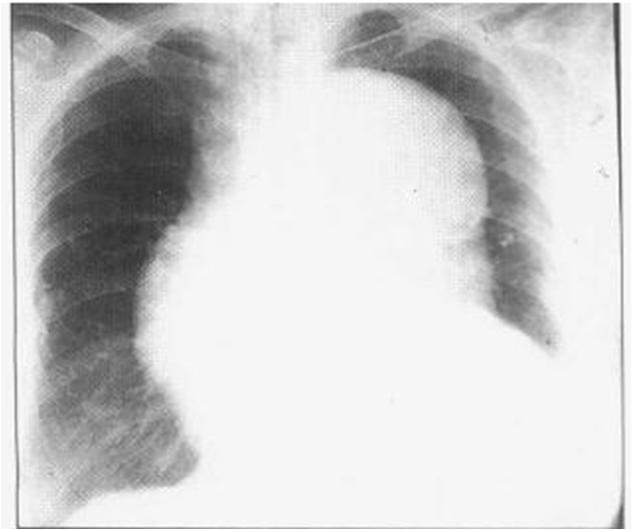

肺栓塞患者胸片示:右下肺起契状阴影